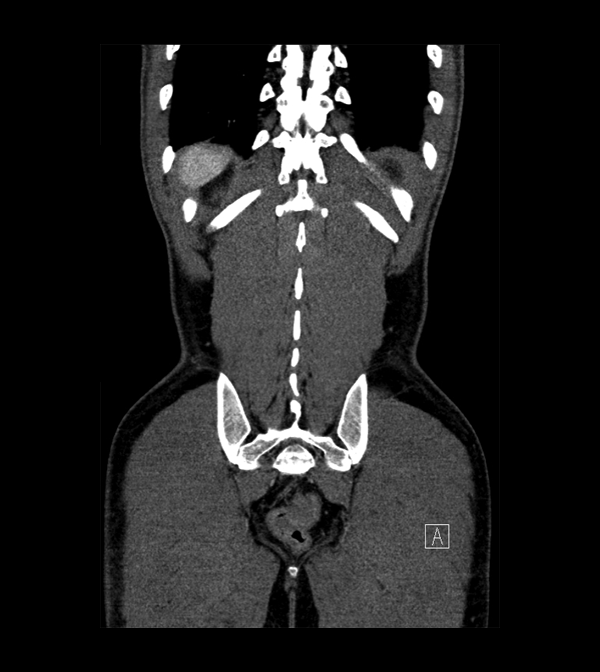

Body

Covers abdominal CT anatomy.